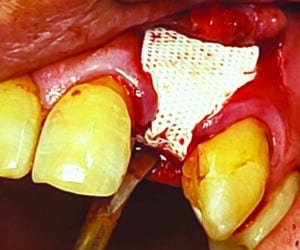

Une fois la partie supérieure des implants dégagée, les vis de couverture sont enlevées et la membrane est coincée sous la berge linguale et mise de façon à recouvrir les implants. Les vis de couvertures sont passées à travers les deux trous et vissées dans les implants (Fig.2).

Fig.2 : Mise en place de la membrane maintenue dans ce cas par les vis de cicatrisation.